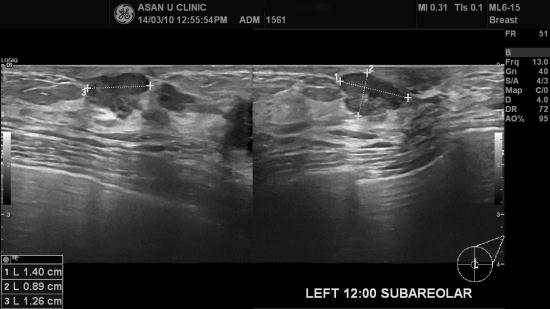

분만과 모유수유중에 생긴 몽울로 생각하다

좌측 유방몽울이 풀리지 않아 검사하시게 된 만 42세의 여성분입니다.

안타깝게도 좌측 유두에 그림과 같은 혹과,

그로부터 2cm 떨어져 바깥쪽으로 2.4cm의 혹이 있었고

좌측 겨드랑이에 림프절비대소견이 있었습니다.

각각 조직검사 및 세포검사하여 유방의 침윤성 유관암과

좌측 액와림프절전이라는 결과를 받았습니다.